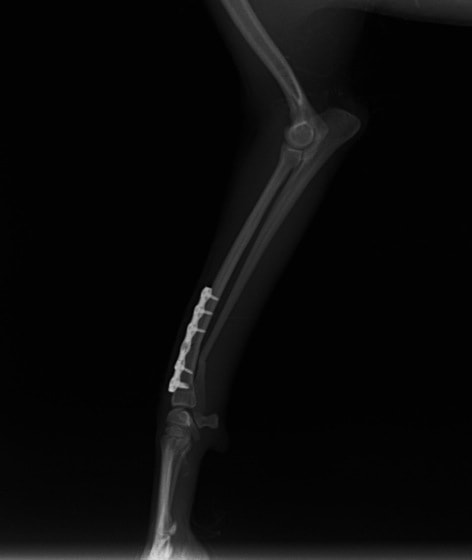

症例:交通事故による椎体脱臼

柴犬:9歳、避妊雌

交通事故直後、胸腰部に激しい疼痛、両後肢に完全麻痺を認め、シェフシェリントン徴候を呈していました。レントゲン検査において、第11-12胸椎間の脱臼が認められました。

脊髄の減圧、脊柱管の再構築・安定化を目的に、片側椎弓切除術およびMatrixMANDIBLE Plateによる椎体固定を実施しました。

隣接椎体を架橋するようにプレートを設置しました。

術後レントゲン写真

※当院にはMatrixMANDIBLE Plate以外のロッキングプレートシステムもいくつか用意があり、症例の性格や活動性、骨折部位によって使い分けています。